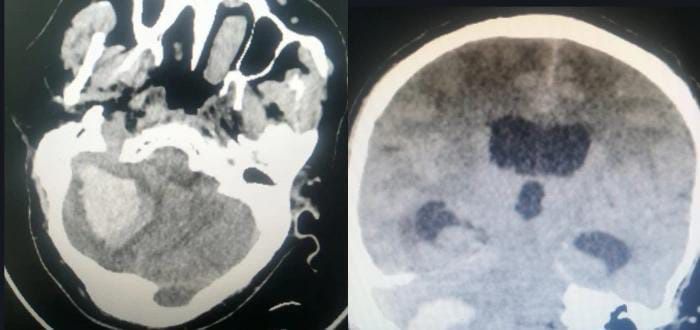

وقالت  الصحة  في  جازان  أن أطباء جراحة الأنف والأذن والحنجرة بمستشفى الملك فهد المركزي بجازان - بفضل الله – تمكنوا من النجاح بإجراء عملية ترميم لقاع الجمجمة الجانبي وانسجة الدماغ والأذن لمريض تم احالته من أحد مستشفيات المنطقة الطرفية كحالة عاجلة تعاني من مرض تآكل شديد بعظمة الأذن ودهليز الأذن والقنوات الهلالية وصولاً لعظم القوقعة وعظم الجمجمة الجانبي وصولاً إلى أنسجة الدماغ مما أدى إلى نزولها جزئياً للأذن.

وقال الفريق الطبي المعالج للحالة أنه تم خلال العملية إستخدام المايكروسكوب الجراحي وجهاز ملاحة الأعصاب مع ترميم كامل لقاع الجمجمة الجانبي من خلال الأذن وفصل التجويف الدماغي عن الأذن وترميم عظم الأذن ، ليتم بعدها نقل المريض لقسم العناية المركزة ومتابعة وضعه الصحي من قبل الأطباء وفرق التمريض وحتى خروجه بالسلامة بإذن الله من المستشفى .